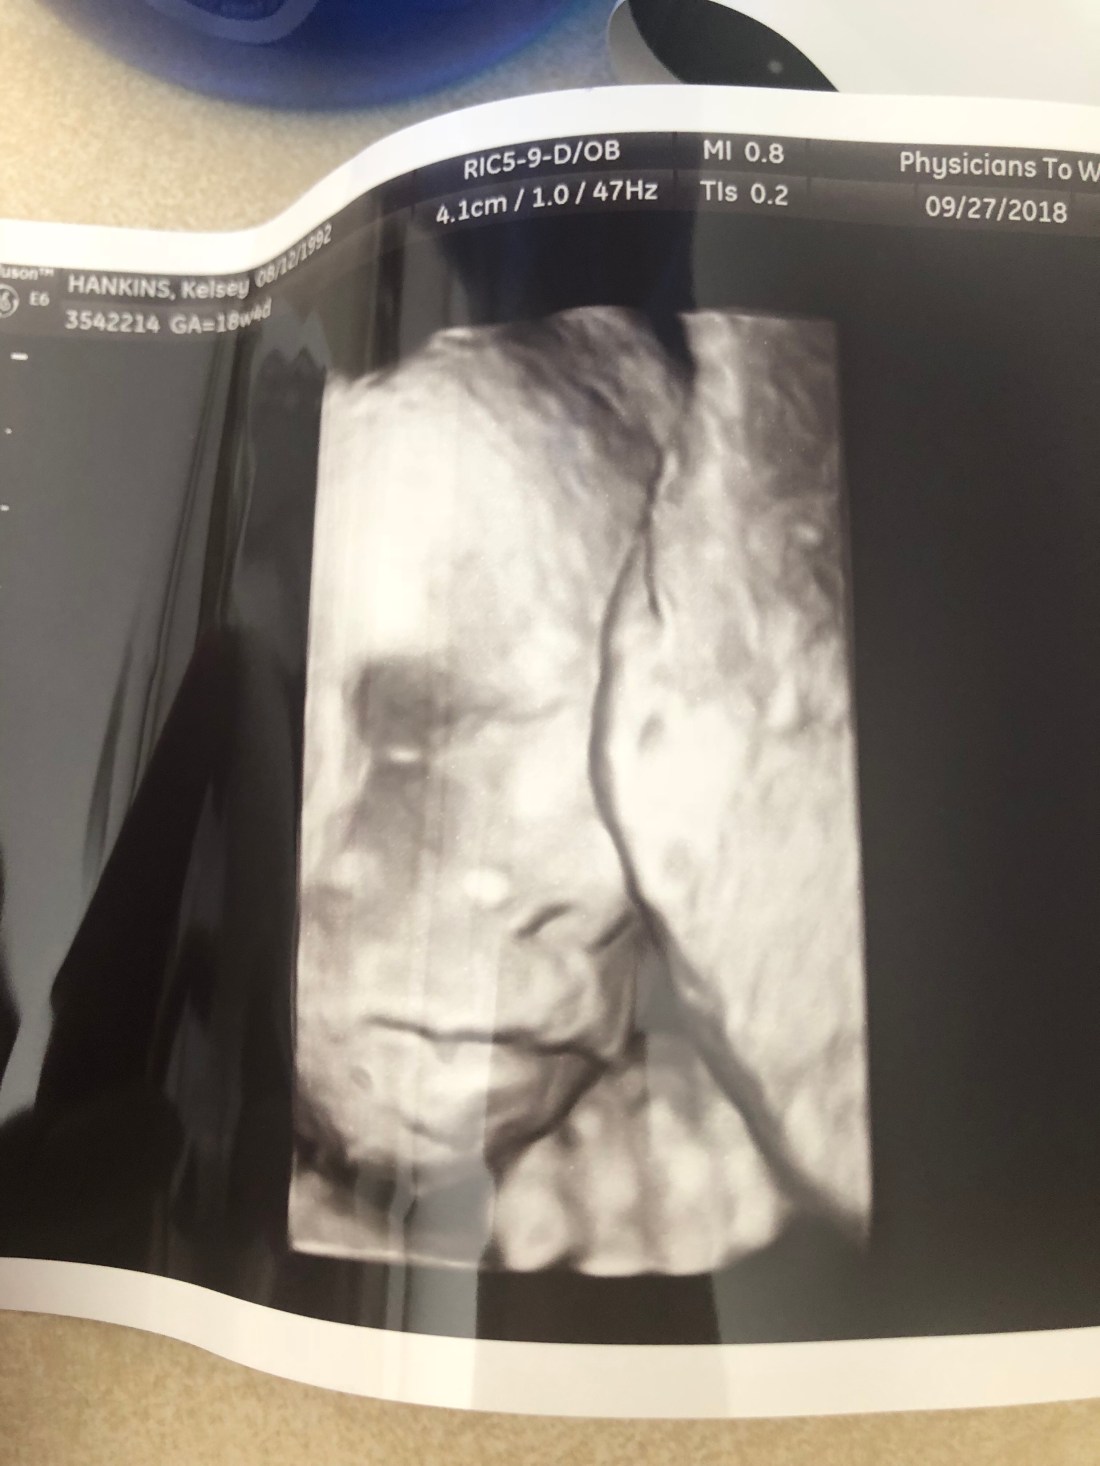

With only one trimester left, I am truly soaking it all in, the last few months with just my husband and I, a full nights rest, belly kicks, crazy cravings, alone time, and life before motherhood. Before we know it, I’ll blink and my sweet boy will be here.